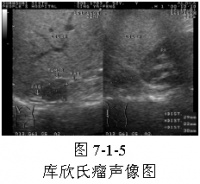

4、B超 方便有效。对肾上腺皮质肿瘤的定位诊断的正确率可达90%以上。